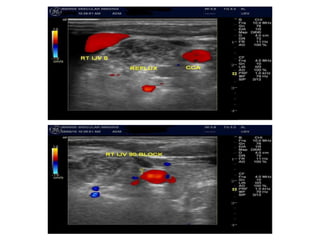

CRITERION 1:

Reflux in the IJV and/or VV

a) Bidirectional flow in one or both of

the IJVs in both postures or

bidirectional flow in one position

with absence of flow in the other

position.These findings suggest

IJV stenosis.

b) Reversal or bidirectional flow in

one or both of VVs in both

positions.These findings suggest

stenosis in the azygos vein, based

on reports controlling the Doppler

parameter in comparison with

catheter venography

a) Flusso bidirezionale in una o in

entrambe le Vene Giugulari interne

in posizione supina (0°) e seduta

(90°) o flusso bidirezionale in una

posizione con assenza di flusso

nell’altra posizione (situazione

suggestiva di stenosi della vena

giugulare).

b) Flusso invertito o bidirezionale in

una o in entrambe le Vene

Vertebrali in posizione supina a 0°

e in quella seduta a 90°: situazione

suggestiva di una stenosi

della Vena Azygos.

Reflusso nelle Vene Giugulari Interne (VGI) e/o nelle Vene Vertebrali (VV):

A: MALFORMAZIONE TIPO SETTO DELLA

VGI DX

B: CIRCOLO COLLATERALE SIGNIFICATIVO